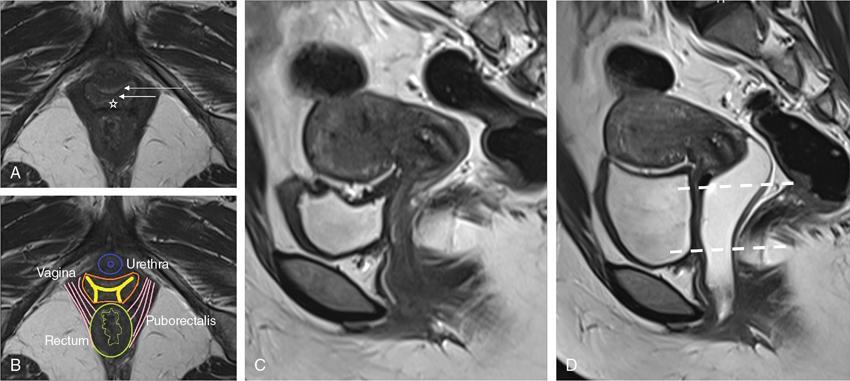

VAGINAL CYSTS Sumeena The vagina is a fibromuscular sheath. Vagina extends from uterus to the vulvar vestibule. The vagina is located in the middle compartment of the pelvis and it is related anteriorly to bladder and urethra, posteriorly to lower rectum and anal canal. The length of vagina ranges from 4 to 12 cm. The posterior wall of vagina is longer and it ends in posterior fornix; the anterior wall is shorter and ends in the anterior fornix. The wall of vagina is composed of three layers: (a) The mucosa consists of nonkeratinized stratified squamous epithelium without glands and its hormone sensitive layer; (b) the muscularis made up of connective tissues and smooth muscle; and (c) the adventitia, which is fascia that connects the vagina to the surrounding pelvic structures and maintains support. The prevalence of vaginal cysts is estimated to be less than 1%. They typically present in the age of 30–40s. Their origin may be Müllerian, Wolffian, squamous or urogenital. Risk factors for vaginal cysts: The vagina may be underevaluated due to probe positioning in routine pelvic US and due to poor vaginal tissue characterization in CT examinations. Though MR imaging provides good tissue characterization, we must focus on the vaginal region to identify any incidental findings. The strengths and limitations of each imaging modality must be understood in assessing the vagina. US is the first-line imaging modality since it is readily available, cost-effective, high resolution and no ionizing radiation. Limitations include operator dependence and patient obesity. The major limitation with transabdominal approach is that the upper portion of the vagina is seen well; the inferior aspect of the vagina is obscured due to shadowing from the pubic symphysis. Limitation with transvaginal US is that the transducer is typically placed in the anterior or posterior fornix which bypasses the perineum and vagina. US imaging needs methodic evaluation performed from introitus to the fornices and include transabdominal, transvaginal and translabial approaches. Due to the poor vaginal tissue characterization and ionizing radiation, CT is usually not indicated for evaluation of the female pelvis. When US is inconclusive, pelvic MR imaging is recommended. The vaginal wall anatomy is best imaged with T2-weighted sequences. The vaginal mucosa has high signal intensity, circular and longitudinal muscle layers have intermediate signal intensity. Embryonic Traumatic Epithelial inclusion cyst/epidermal inclusion cyst/squamous inclusion cyst Skene’s duct cysts Urethral diverticulum Infective Filariasis Vaginitis emphysematosa Epidermoid cyst Sebeceous cyst Endometriotic cyst Ciliated cyst Paraurethral mass Rare Lymphangioma Postradiation Haematocolpos Rectocele and cystocele Prolapsed ectopic ureterocele Large nabothian cyst, tunnel cluster cysts Adenoma malignum Most common type of vaginal cysts, almost up to 40% of cystic masses. As Müllerian epithelial tissue can present anywhere in the vaginal wall, the cysts can also be found anywhere within the vaginal walls. Most common location is along the anterolateral aspect of the vagina. Müllerian cysts present as small, midline cystic masses, with no symptoms and require no treatment. Symptomatic vaginal cysts are treated by excision. The entire cyst wall must be removed to prevent recurrence. Adenocarcinoma can arise in a Müllerian vaginal cyst. The epithelium of Gartner’s cysts is devoid of cytoplasmic mucicarmine and PAS-positive material, in contrast to the epithelium of Müllerian cysts. MRI – Gold standard. Mucus secretion is a unique feature of Müllerian cysts and shows heterogeneous T2 signal. Extent of the cyst, surrounding structures are better evaluated in MRI prior to surgery. Incomplete regression of Wolffian ducts leads to the development of Gartner duct cysts. They are usually noted in the upper anterolateral wall of the vagina above the inferior border of the pubic symphysis. Typically less than 2 cm. When these cysts are large enough, they can compress the urethra causing urinary symptoms. It can also be associated with abnormalities of the metanephric urinary system such as an ectopic ureter, unilateral renal agenesis and renal hypoplasia. USG: Anechoic structure in the upper vagina; transvaginal US provides better differentiation than the transabdominal approach. Fig. 11.19.1.1; T2-axial image shows hyperintense cystic lesions, one in posterior fornix and another one in anterior aspect of upper vagina. Both the lesions are above the level of pubic symphysis. Fig. 11.19.1.2; T2-sagittal image shows hyperintense cystic lesions, one in posterior fornix and another one in anterior aspect of upper vagina. Both the lesions are above the level of pubic symphysis. Bartholin glands are commonly located posterolateral to the vaginal introitus and medial to the labia minora. The obstruction of the gland’s duct either by a stone or a stenosis, which may be caused by prior infection or trauma, leads to Bartholin gland cysts. Cysts are typically round and unilocular, seen at or below the level of the pubic symphysis, usually asymptomatic. This is most apparent on coronal plane imaging. USG: Bartholin gland cysts can be imaged by a transperineal approach. Although these cysts are usually asymptomatic, occasional infection may necessitate drainage of the cysts (Fig. 11.19.1.3). Bartholin gland duct can be obstructed due to stone or stenosis, later which can become infected. The Bartholin’s gland abscess size ranges from 2 to 8 cm with an average of 3 to 4 cm. Antibiotics with or without surgical drainage is the treatment. Marsupialization may be needed in recurrent conditions. USG-complex cystic hypoechoic to anechoic lesions increased throughout transmission. Colour Doppler may show peripheral hyperaemia. Spectral flow – low resistance arterial flow. MRI-T2: Tends to show heterogeneous signal T1 C+ (Gd): pericystic enhancement may be seen (Fig. 11.19.1.4). Vaginal inclusion cysts – also known as epidermal inclusion cysts, most commonly are seen in the distal posterior or lateral vaginal wall at sites of previous trauma or surgery. Inclusion cysts are lined by a stratified squamous epithelium and contain keratinous material. Symptomatic cyst needs treatment. The treatment of choice for symptomatic cysts is marsupialization. MRI-DWI shows restriction (Fig. 11.19.1.5). Skene glands are paired structures in periurethral location near external urethral meatus with ducts draining into the urethra. Skene gland cysts can cause UTI or urethral obstruction. They are distinguished from urethral diverticulum, which are usually midurethral. In T2-weighted images, Skene duct cysts seen as round or oval hyperintense lesions just lateral to the external urethral meatus. MRI:T1 hyperintense due to proteinaceous material. T2 hyperintense. Fluid–fluid level if complicated with debris or haemorrhage (Fig. 11.19.1.6). It may be congenital or result from infection or obstruction. In females, diverticula commonly extends from the posterolateral wall of the mid-portion of the urethra. During voiding cystourethrography (VCUG), they are seen best on postvoid images. Transrectal US shows a cystic mass in proximity to the urethra and it will be seen anterior to the vagina. Lack of radiation and capacity to differentiate solid from cystic masses is the advantage of US over CT. CT shows a periurethral lesion with low attenuation. MRI shows T1 hypointense and T2 hyperintense fluid signal intensity. Postcontrast imaging with gadolinium is used to evaluate infection or inflammation. Adenoma malignum of the cervix is a rare variant of cervical mucinous adenocarcinoma. VAGINAL MALIGNANCIES Rupa Renganathan, Suchana Kushvaha The primary vaginal carcinoma is a very rare gynaecological malignancy and accounts for 2%–3% of genital tract malignancies and 10% of all vaginal malignancies. It is defined as a cancer found in the vagina without histological or clinical evidence of cervical or vulvar malignancy and without previous history of treatment of cancers in the last five years. The commonest primary carcinoma is squamous carcinoma, and other rare primaries are adenocarcinoma, melanoma and sarcomas. The secondaries in the vagina are much more common than the primary and account for more than 80% of vaginal malignancies. Primary vaginal carcinoma is common in elderly, however, seen in the younger women when associated with human papillomavirus (HPV 16 and 18). Vaginal carcinomas are staged based on FIGO classification. Management of the cancer is usually based on the stage of the disease and the histological subtypes. Vagina is an elongated fibromuscular structure connecting the uterus with the vulva. It is approximately 7–9 cm long. The long axis is oriented 90 degrees to the uterine axis and its upper part is oriented almost horizontally and in plane with the pelvic floor. It is lined by the nonkeratinizing stratified squamous epithelium. It has anterior, posterior and lateral walls. The upper portion of vagina is invaginated by the cervix such that a space is created between its walls and the cervix called fornices. The posterior fornix is deeper than the anterior fornix. Anterior wall is separated from the bladder base and the urethra by the anterior vesicovaginal septum while the posterior wall is separated from the rectum by rectovaginal septum. The posterior fornix is covered with the peritoneal reflection that forms the Pouch of Douglas. It is supplied by the vaginal arteries, originating from the internal iliac artery and branches of uterine, middle rectal and inferior vesical arteries. There is considerable overlap in the lymphatics between the various parts of vagina. The upper two-thirds of the vagina drain into the pelvic lymph nodes that include external, internal and common iliac groups and the lower third into the superficial inguinal and femoral lymph nodes. The posterior vaginal wall also drains into the perirectal lymph nodes. MRI is the standard imaging modality for local staging of cancers and also for assessment of treatment response and surveillance due to superior soft tissue resolution, multiplanar capability. In a relaxed state, it is seen as a ‘H’ shaped structure posterior to urethra with the anterior and posterior walls being opposed to each other. The vaginal lumen may have secretions or blood-causing distention of its lumen. The anatomy of the vagina is best depicted on T2w images where three layers of its wall can be distinguished in a nondistended state. The mucosa is T2 hyperintense with a hypointense submucosal and muscularis layer beneath it. It is surrounded by adventitia which is hyperintense due to the venous plexus (Fig. 11.19.2.1A and B). For accurate staging purposes, vagina should be distended with ultrasound gel with the help of a syringe and infant feeding tube (Fig. 11.19.2.1C and D). Before inserting gel, patient consent must be taken and her marital status should be enquired. Care must be taken that air is not insufflated while introducing the jelly. Jelly can also be introduced in patients other than carcinoma vagina in cases where vaginal involvement is suspected in other malignancies. After adequate distention, the walls get separated and the fornices are better delineated. For staging purposes, the vagina is divided into three parts. The upper one-third lies above the level of the bladder base and includes the fornices. The middle one-third is opposite to the bladder base and the lower one-third opposite to the urethra (Fig. 11.19.2.1D). Ultrasound owing to its limited field of view and inaccurate staging is not used for imaging of vaginal pathologies. CT has poor contrast resolution and is used only for lymph nodes staging in known patients of vaginal malignancy. PET CT has the advantage in that it combines both the functional and anatomical information about the tumour. While performing PET for the gynaecological malignancies, general measures to reduce bladder activity, like Foley’s catheterization, IV hydration and diuretic administration, are adapted and the image acquisition is done from the pelvis cranially. The advantage of PET beyond providing functional information is that it provides information about distant metastases. The presence of nodal metastases in patients with vaginal cancers portends a poor prognosis and alters the management. In a study by Christensen et al., PET CT was found to be more sensitive and carried greater negative predictive value as compared to MRI for detection of lymph nodes. However, commonly seen inflammatory and the reactive lymph nodes may show uptake. Node biopsy or excision is mandatory wherever the metastatic involvement is indeterminate or questionable. PET CT is recommended for restaging the recurrent tumour, and differentiating the treatment changes from recurrence in vaginal carcinomas. In cases of vaginal sarcomas, it is used for grading, staging and follow-up imaging. MRI is the main investigation for evaluation of vaginal masses and for both staging and surveillance. Patients are requested to be fasting for at least 4 hours to limit bowel motility and to empty the bladder 1 hour before the study to achieve moderate distention of the bladder. Use of antispasmodic agents like Butylscopolamine 40 mg IM/IV or Glucagon 0.5–1 mg IV/IM can also be considered to reduce bowel movements. The vagina should be distended with about 60 mL of Ultrasound Gel for evaluation of vaginal lesions. The patient is imaged in supine position with phased array abdomino pelvic coil. The saturation band is usually placed anterior and superior to the field of view. T2 imaging remains the mainstay for evaluation of vaginal tumours. The basic sequences for evaluation of vagina lesions are T2 sagittal, axial, coronal and oblique axial, T1 axial and diffusion-weighted imaging in axial plane. The high-resolution oblique axial along the plane of vagina is the best sequence which demonstrates the tumour and its extent. The study may be completed by contrast injection. The sequences for contrast evaluation will include pre-T1 with fat saturation, followed by dynamic contrast injection and postcontrast T1 fat saturated acquisition. The most common clinical presentation would be painless vaginal bleeding (65%–80%) followed by vaginal discharge, pelvic pain, urinary symptoms and mass being felt in the vagina. The primary carcinoma are usually squamous cell carcinoma and accounts for about 80% of cases. They are more commonly seen in the upper third in the posterior wall. It is associated with HPV and about 30% of women also have history or associated intraepithelial and invasive cancers of cervix and vulva. About a third of patients present with lymph nodal metastasis in the pelvis or inguinal region at the time of clinical presentation. Adenocarcinoma accounts for only 9% of primary vaginal malignancies, and they are usually seen in the anterior wall of the upper third of the vagina. They affect younger age group (14–21 years) and arise from the lesions such as endometrial deposits and the vaginal adenosis. About two-thirds of the cases have exposure to Diethylstilbestrol to their mothers. When seen in older women, they are usually clear cell carcinomas. Staging of vaginal carcinoma with MRI parallels clinical FIGO staging (Figs 11.19.2.2–11.19.2.4). The tumour is best seen on T2-weighted sequences where it is seen as an intermediate signal (higher than muscle and lower than fat). Adenocarcinomas typically exhibit high T2 signal. Because of the signal on T2, the tumour is well delineated from the vaginal wall which displays low signal intensity. When the tumour is limited to vagina, it is difficult to be seen on T1 sequences unless it causes a contour abnormality as the tumour will be isointense on T1. Stage I tumours are those which are either seen as mass/plaque like thickening but will be limited to vagina and will be diagnosed if the hypointense T2 signal of the vaginal wall is preserved (Fig. 11.19.2.5). When the tumour disrupts this hypointense layer and extends into the paravaginal fat, the staging becomes Stage II (Fig. 11.19.2.6). The loss of normal signal of the vaginal wall should be looked at all three orthogonal planes to identify subtle loss of the signal which is the important finding which upstages the tumour.